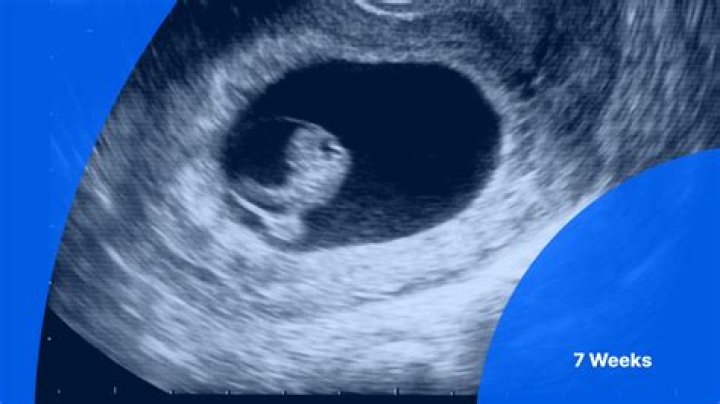

You may start to feel bloated and your breasts may start getting bigger. Your baby is growing, too. Baby’s head and face are developing and tiny hands and...